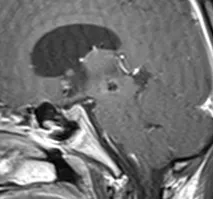

20岁大学生中脑海绵状血管瘤病例呈现突发昏迷症状。术前MRI评估显示病变范围,术后MRI确认切除效果,术后1年随访记录恢复情况。

鉴于病变位置深在,解剖关系高度复杂,加之该区域神经核团和传导束分布密集,手术风险极高。此外,中脑等脑干海绵状血管瘤易于反复出血,为最大限度挽救患者生命并提升生活质量,通常采用显微外科手术作为治疗手段。

基于轴向平面上的位置观察,病变可大致分为以下几类:仅中脑角(A1)、仅被盖(A2)、仅顶盖(A3)、脑角和被盖(A4)、被盖和顶盖(A5),以及所有三个区域(A6),包括中脑脚、被盖和顶盖(图1)。根据每个中脑部分内的确切位置及其轴向和矢状范围对中脑海绵状血管瘤(MCM)进行位置分类,进而采用不同的手术入路,这对术后效果至关重要。